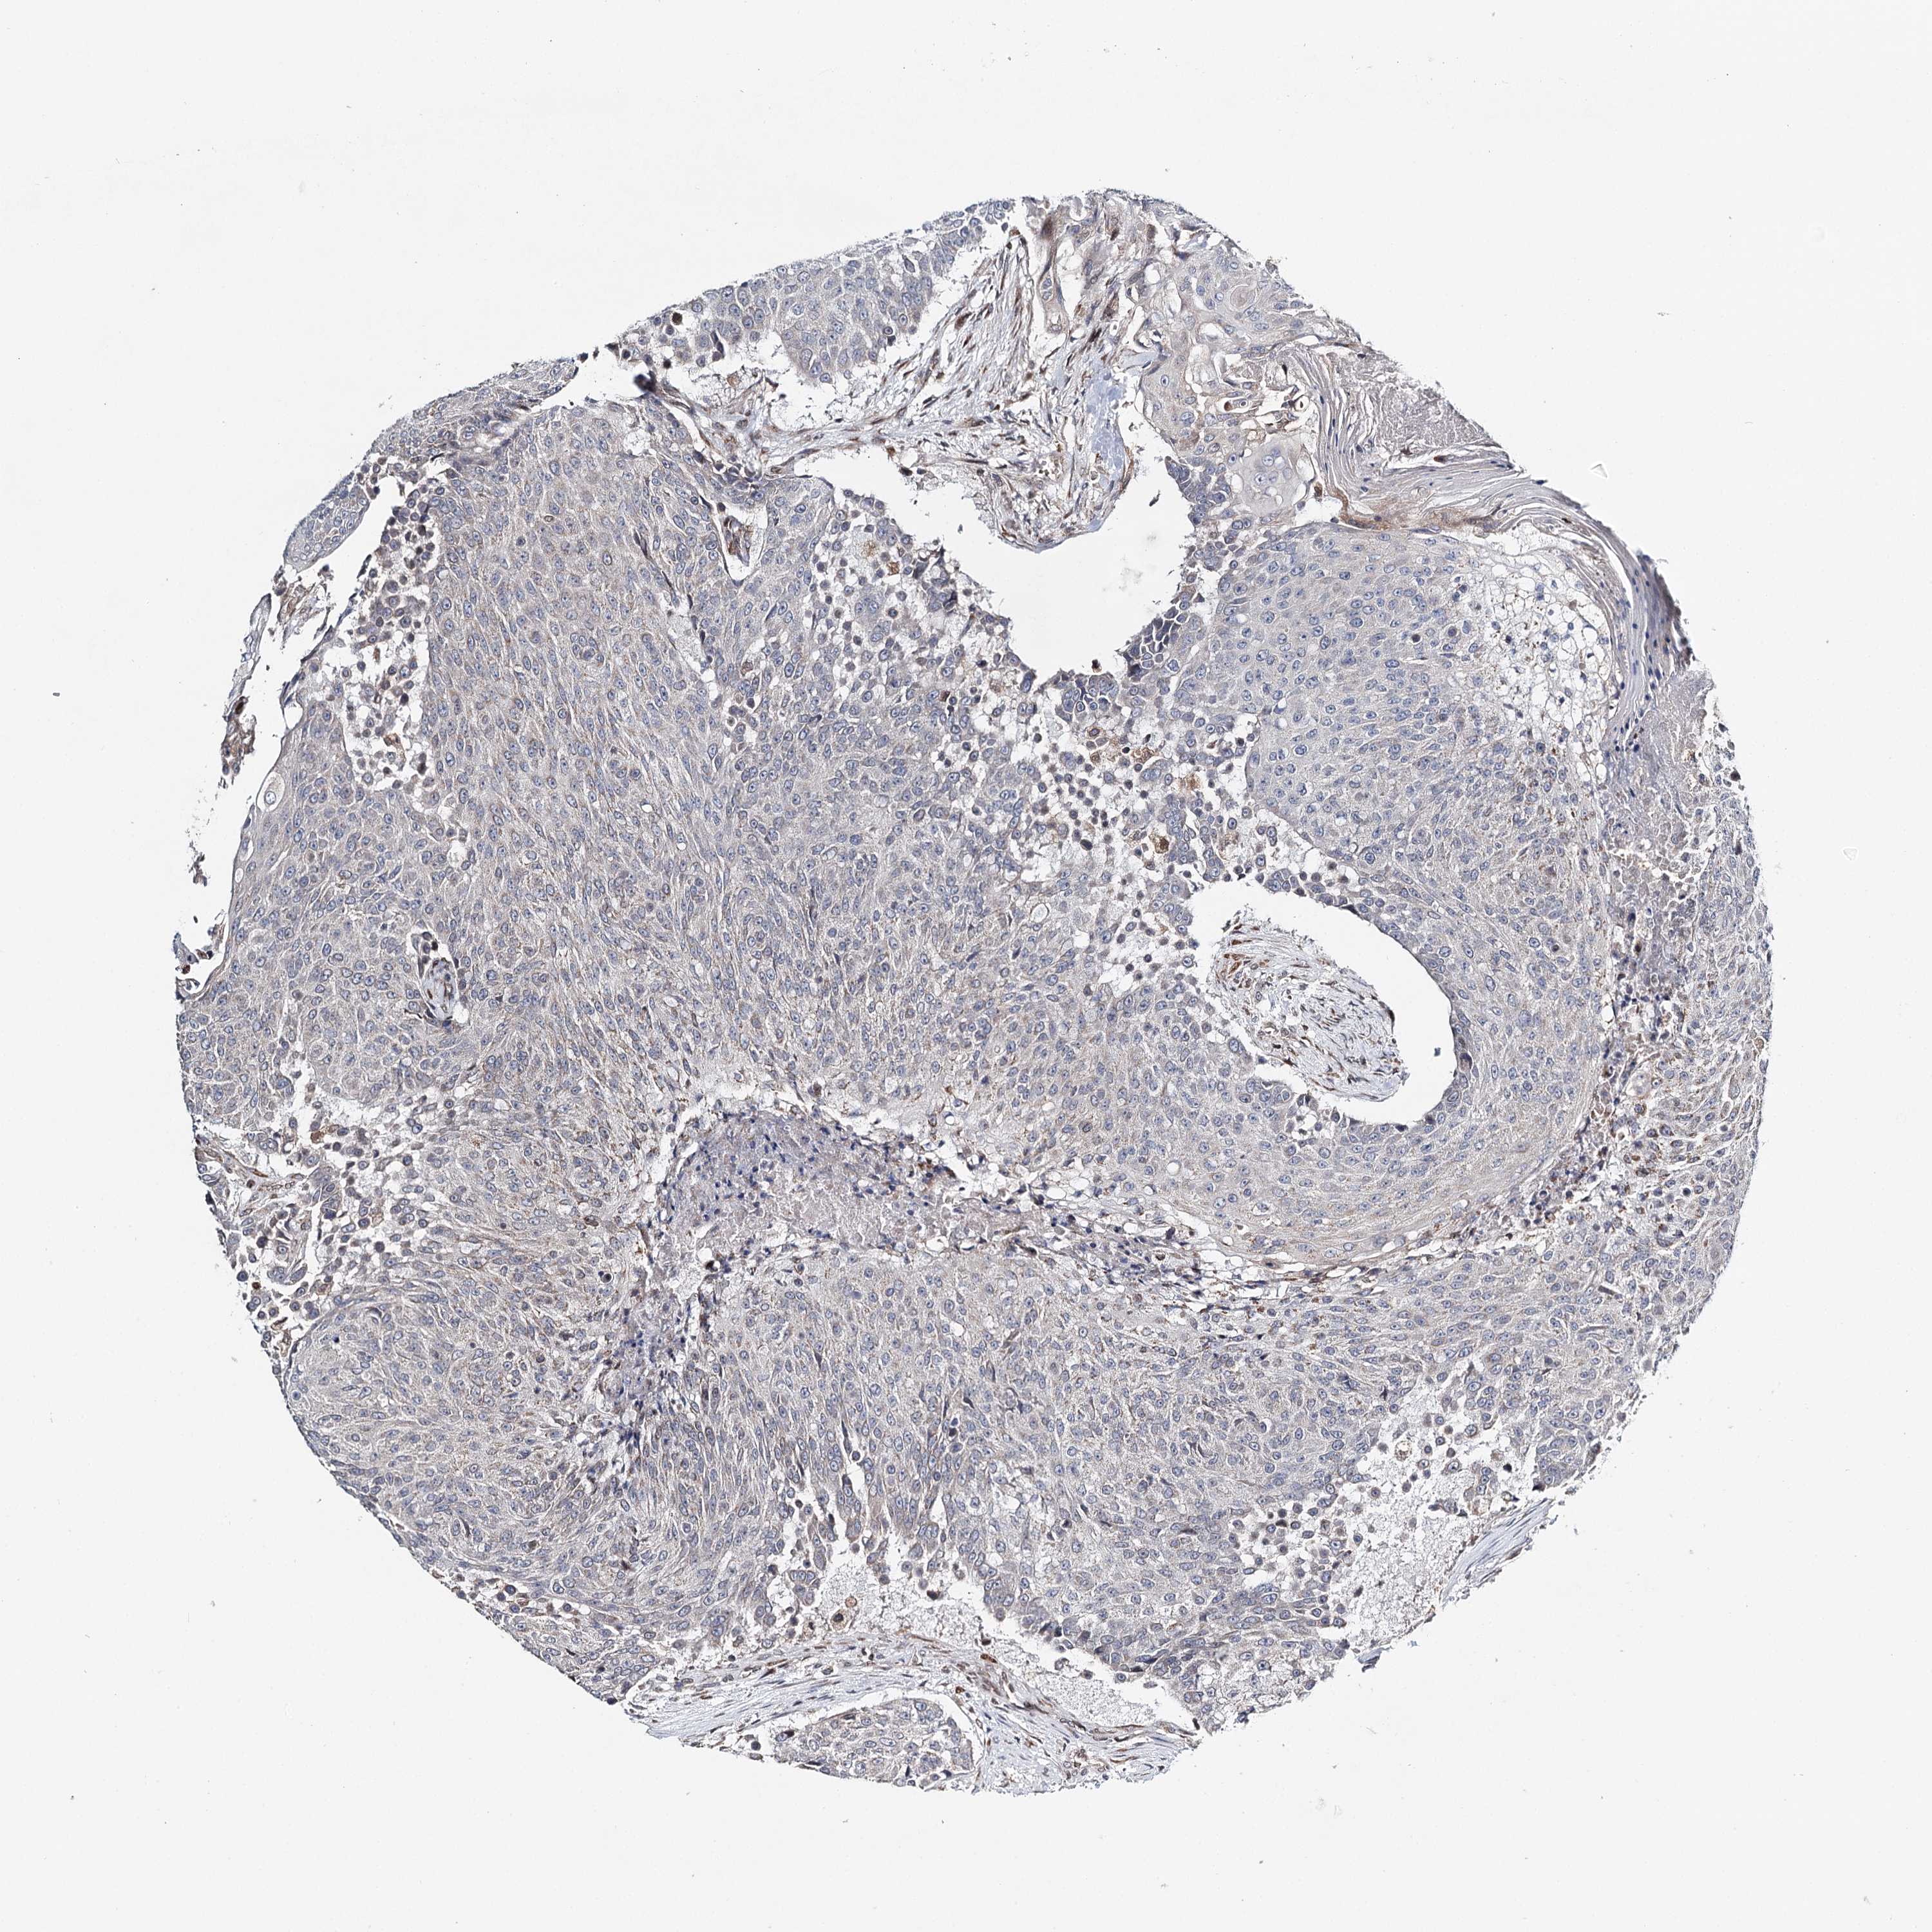

UROTHELIAL CANCER - Protein expressioni

A mouse-over function shows sample information and annotation data. Click on an image to view it in a full screen mode. Samples can be filtered based on level of antibody staining by selecting one or several of the following categories: high, medium, low and not detected. The assay and annotation is described here.

Note that samples used for immunohistochemistry by the Human Protein Atlas do not correspond to samples in the TCGA dataset.

Antibody stainingi

Antibody staining in the annotated cell types in the current human tissue is reported as not detected, low, medium, or high, based on conventional immunohistochemistry profiling in selected tissues. This score is based on the combination of the staining intensity and fraction of stained cells.

Each image is clickable and will lead to virtual microscopy that enables deeper exploration of all samples and also displays staining intensity scores, fraction scores and subcellular localization as well as patient and tissue information for each sample.

Antibody HPA037786

Antibody HPA038034

Antibody HPA038867

Antibody HPA038868

Staining

High

Medium

Low

Not detected

Intensity

Strong

Moderate

Weak

Negative

Quantity

>75%

75%-25%

<25%

None

Location

Nuclear

Cytoplasmic/membranous

Cytoplasmic/membranous,nuclear

Urothelial carcinoma, High grade

Urothelial carcinoma, Low grade

Urothelial carcinoma, NOS